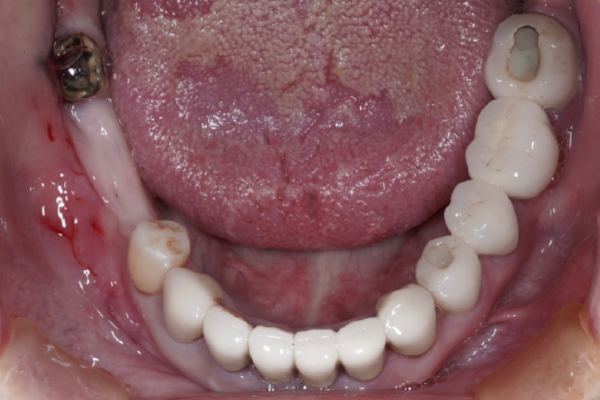

【お悩み】

奥歯を失ったまま過ごしていましたが、「手術が怖い」「本当に大丈夫なのか不安」という気持ちから治療に踏み切れずにいました。

【診断】

CT検査を行い、インプラント治療が可能な骨の状態であることを確認しました。

【治療内容】

治療前にしっかりと説明を行い、患者さまにご納得いただいたうえでインプラント治療を進めました。

【治療後】

治療後は違和感も少なく、「もっと早く相談すればよかった」とお話しされています。

【この症例のポイント】

不安を感じている方こそ、まずは状態を正確に知ることが大切です。

治療を受けるかどうかは、相談後に決めていただけます。